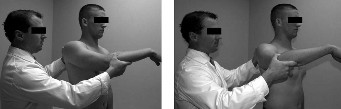

The correct answer is (C). Each RC tendon has specific tests for pathology. The supraspinatus strength test (aka Jobe test) is performed by abducting the shoulder to

90 degrees, bringing the arm in the scapular plane (30 degrees forward), and maximally internally rotating the arm (thumb pointing to the floor) (Fig. 2–1). The test is positive if weakness is found or if pain is experienced. Another test for the supraspinatus is the drop arm test. In the drop arm test, the arm is passively elevated by the examiner to the Jobe position, the patient is asked to attempt to keep it there, and the arm is released by the examiner. The test is positive if the patient is not able to keep the arm elevated and the arm drops.

Figure 2–1 Jobe test.

The belly press test (Answer A) and lift off test (Answer D) are used to evaluate for subscapularis pathology (Figs. 2–3 and 2–4). The hornblower test (Answer B) assesses the teres minor (Fig. 2–2). The external rotation lag test (Answer E) evaluates the infraspinatus.

Figure 2–3_Positive lift-off test with the patient’s left arm in the right picture. Negative lift-off test with the patient’s right arm in the left picture. (From Lyons RP, Green A. Subscapularis tendon tears. _J Am Acad Orthop Surg. 2005;13(5):353–363.)

Figure 2–4_Positive belly-press test with the patient’s left arm in the right picture. Negative belly-press test with the patient’s right arm in the left picture. (From Lyons RP, Green A. Subscapularis tendon tears. _J Am Acad Orthop Surg. 2005;13(5):353–363.)